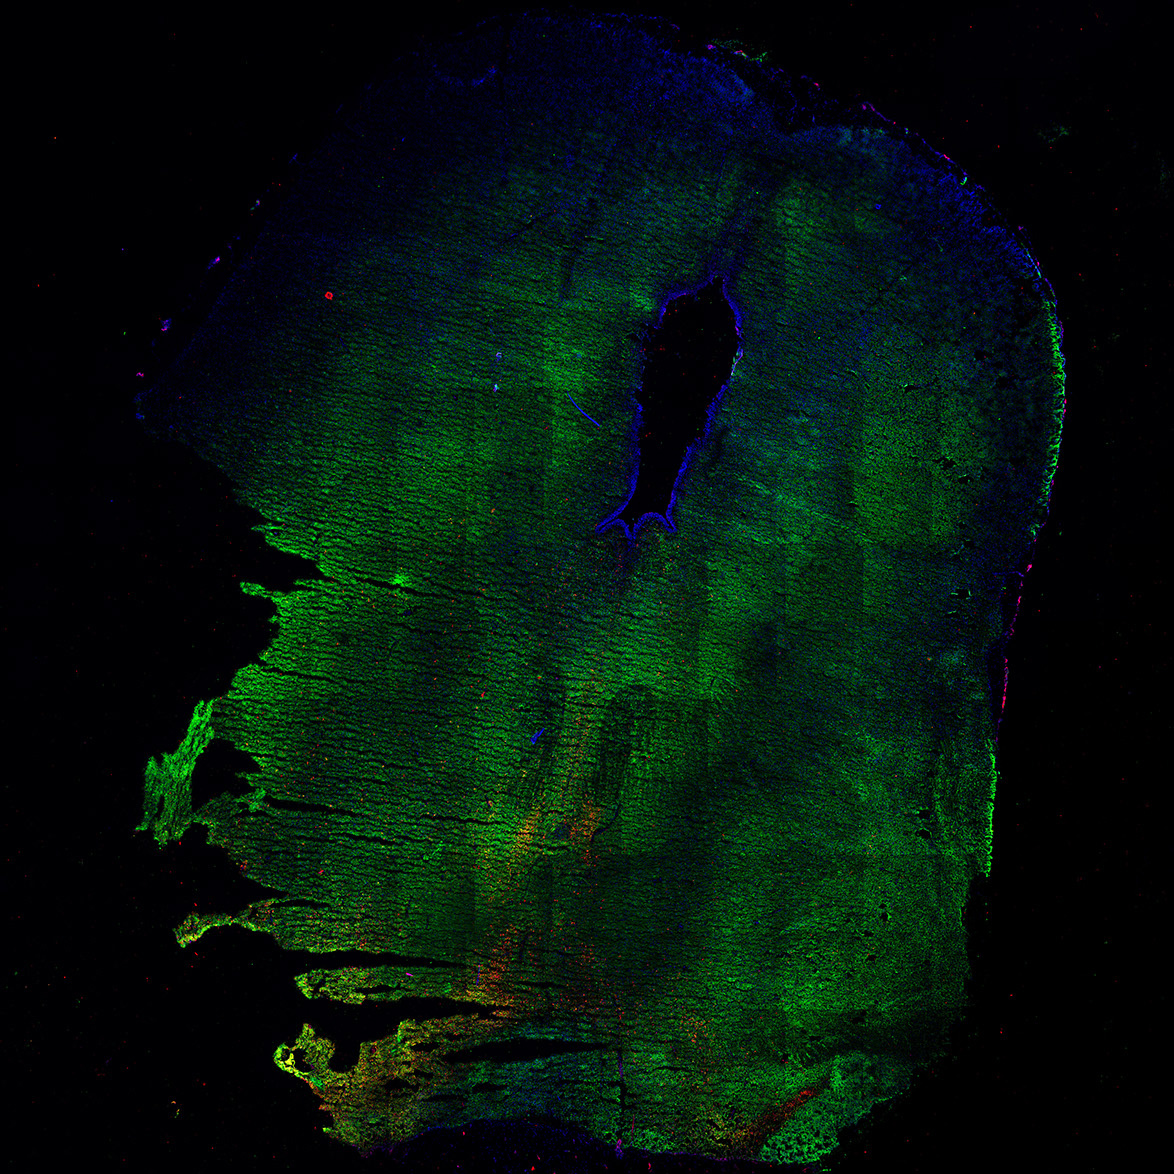

An anatomical analysis of the developing human midbrain from 6 post-conceptional weeks (PCW) to 22 PCW reveals increased tissue complexity, characterized by the emergence of dopaminergic nuclei, as highlighted by immunofluorescence analysis for tyrosine hydroxylase (TH).

11PCW

DAPI

11PCW human midbrain

MAP2

SOX2

Merged